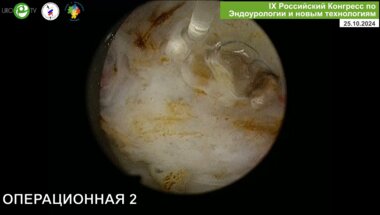

Бурлака О.О. - Лазерная энуклеация простаты

Бурлака О.О. - Гольмиевая высокоэнергетическая энуклеация простаты с технологией Moses (HoLep)